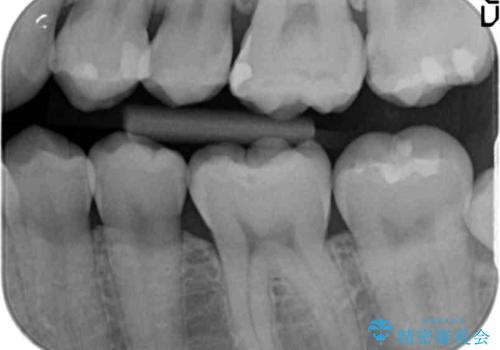

奥歯の虫歯治療でしたが、プラスチック周りと、歯と歯の間が大きな虫歯になっていました。

インレーでの修復予定でしたが、歯と歯の間が狭く、正確な型取りが難しい状態でした。

全体矯正をする前の虫歯チェックで見つかった虫歯です。